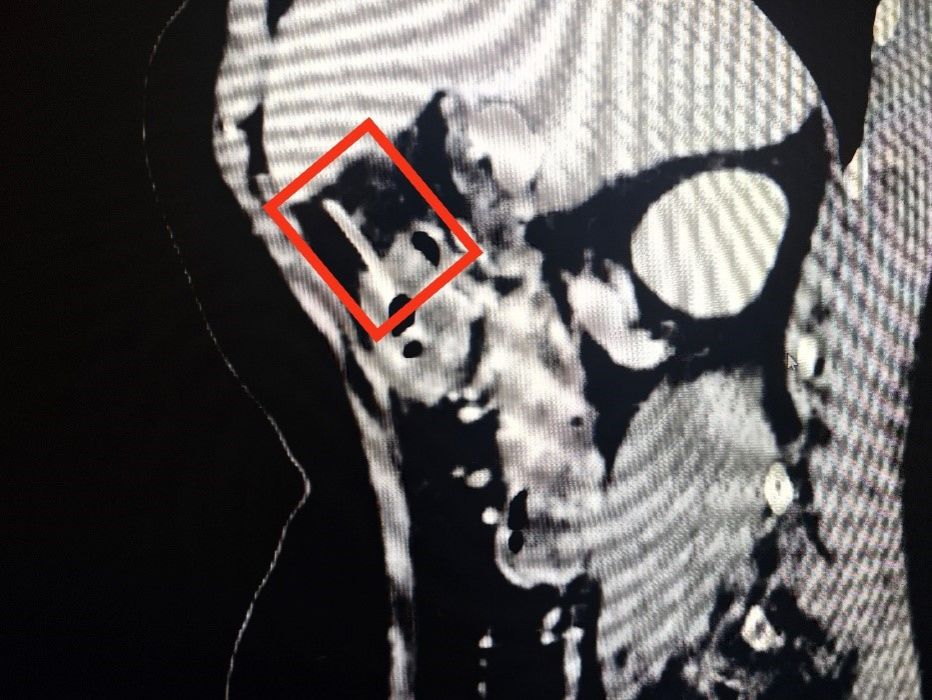

原来,三日前,张大娘和家人边吃鱼边聊天时,没注意鱼刺就吞了下去,本人还没有感觉到异常,所以腹痛难忍时也没有跟医生说明。在为张大娘做了CT检查后,发现胃周腹腔内存在少量游离气体,CT室主任潘历波在查找导致气体产生的原因时,发现了已经穿透胃壁的异物。潘主任就此询问患者病史,有没有吞食过什么尖锐的东西,患者才想起腹痛前三天曾食用过鱼肉。

(CT显示长约5cm的鱼刺已经穿透胃壁)

此时,刺透胃壁的鱼刺可能随时扎入肝脏,引起大出血,危及生命。面对这一棘手问题,黄山平主任考虑取出异物刻不容缓,立即给患者进行胃镜检查。在胃镜探查过程中发现,鱼刺一端已深深扎入胃窦前壁,鱼刺大部分均在胃壁里,仅有很小部分在胃腔内,造成“抓捕”困难,一不小心鱼刺可能会“溜出”胃壁。为此,黄山平主任团队凭借多年积累的丰富经验,精准使用内镜异物钳将鱼刺牢牢抓住,并将其完整拔出,过程顺利,患者腹痛立刻得到缓解。